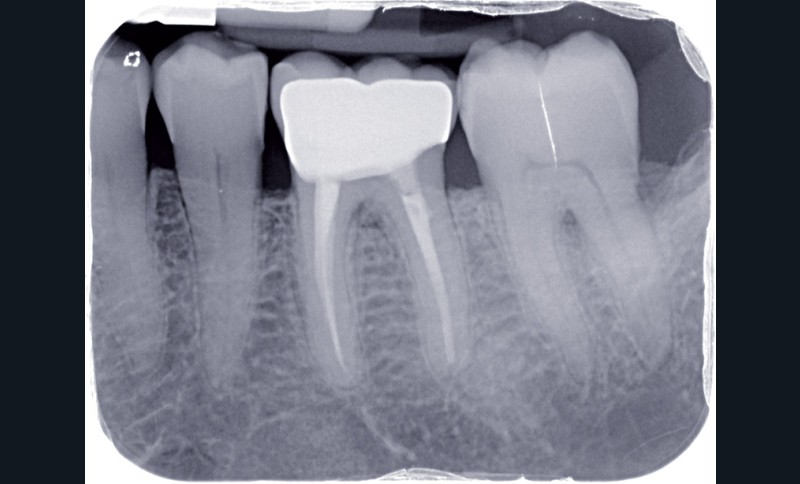

La dentisterie contemporaine privilégie les modes de restauration conservateurs avec pour objectif de préserver la vitalité pulpaire. Cependant, des échecs peuvent survenir du fait de nouvelles agressions et ce, malgré la qualité des procédures opératoires mises en œuvre (fig. 1).

Dans ces situations, le praticien est conduit à dépulper et à restaurer les dents traitées endodontiquement. Les traitements doivent alors s’inscrire dans le concept du continuum endo-restaurateur qui a été défini comme étant « le processus spatio-temporel sans interruption ni rupture qui débute par l’accès à l’endodonte et s’achève avec la mise en place de la restauration prothétique d’usage » (1). Il existe bien une continuité, du traitement endodontique à la restauration fonctionnelle d’usage qui conditionne le pronostic et les résultats du traitement à long terme (fig. 2).